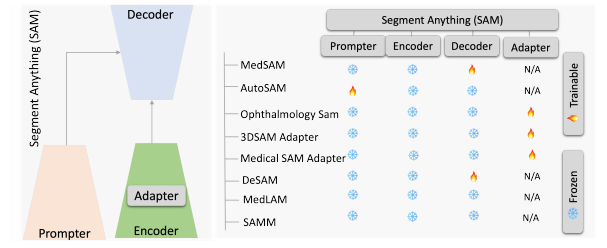

SAM for Medical Segmentation

Medical SAM 总览

- Adapting by Fine-Tuning

MedSAM:通过在大规模医学分割数据集上微调 SAM,创建了一个用于通用医学图像分割的扩展方法 MedSAM。这一方法在 21 个 3D 分割任务和 9 个 2D 分割任务上优于 SAM。

- Adapting through Auxiliary Prompt Encoder

AutoSAM:为SAM的提示生成了一个完全自动化的解决方案,基于输入图像由AutoSAM辅助提示编码器网络生成替代提示。AutoSAM 与原始的 SAM 相比具有更少的可训练参数。

- Adapting Through Adapters

Learnable Ophthalmology SAM

在眼科的多目标分割:通过学习新的可学习的提示层对SAM进行了一次微调,从而准确地分割不同的模态图像中的血管或病变或视网膜层。

3DSAM-adapter

3DSAM-adapter:为了适应3D空间信息,提出了一种修改图像编码器的方案,使原始的2D变换器能够适应体积输入。

Medical SAM Adapter

Medical SAM Adapter:专为SAM设计了一个通用的医学图像分割适配器,能够适应医学数据的高维度(3D)以及独特的视觉提示,如 point 和 box。

- Adapting by Modifying SAM’s Decoder

DeSAM

DeSAM:提出了将 SAM 的掩码解码器分成两个子任务:提示相关的 IoU 回归和提示不变的掩码学习。DeSAM 最小化了错误提示在“分割一切”模式下对SAM性能的降低。

- SAM as a Medical Annotator

MedLAM

MedLAM:提出了一个使用 SAM 的医学数据集注释过程,并引入了一个少量定位框架。MedLAM 显著减少了注释负担,自动识别整个待注释数据集的目标解剖区域。

SAMM

Segment Any Medical Model, SAMM:这是一个结合了3D Slicer和SAM的医学图像分割工具,协助开发、评估和应用SAM。通过与3D Slicer的整合,研究人员可以使用先进的基础模型来分割医学图像。

总体来说,通过各种微调、适配和修改方法,SAM 已被成功适应了用于医学图像分割的任务,涵盖了从器官、病变到组织的不同医学图像。这些方法也突出了将自然图像的深度学习技术迁移到医学领域的潜力和挑战。在未来,SAM 及其变体可能会继续推动医学图像分析领域的进展。